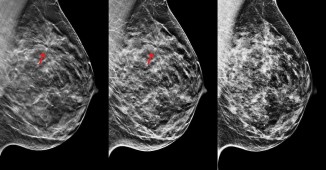

მკერდის კიბო ქალებში ყველაზე გავრცელებული ონკოლოგიური პათოლოგიაა, მაგრამ დაავადების ნაადრევ სტადიაზე დროული თერაპიის დაწყებით, მისი დამარცხება..